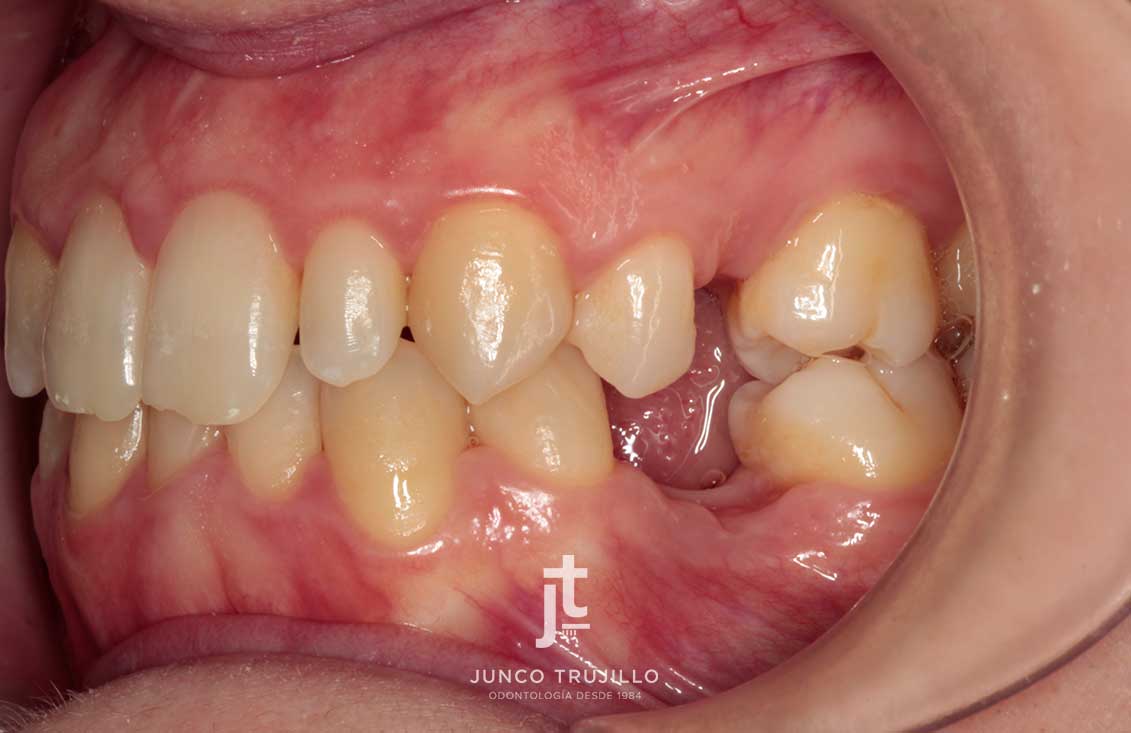

En nuestra clínica realizamos un estudio personalizado con radiografías y escáner 3D para planificar cada tratamiento con precisión. Los Implantes en Palencia permiten recuperar la capacidad de masticar con normalidad, mejorar la pronunciación y evitar la pérdida ósea que se produce tras la ausencia dental. Además, ayudan a mantener la armonía facial y la salud del resto de piezas dentales, evitando que se desplacen.

Casos de implantes

Existen diferentes tipos de Implantes en Palencia según las necesidades de cada paciente. Los implantes unitarios se utilizan para sustituir un solo diente sin afectar a los adyacentes. También existen implantes múltiples, que permiten reponer varios dientes mediante puentes sobre implantes.